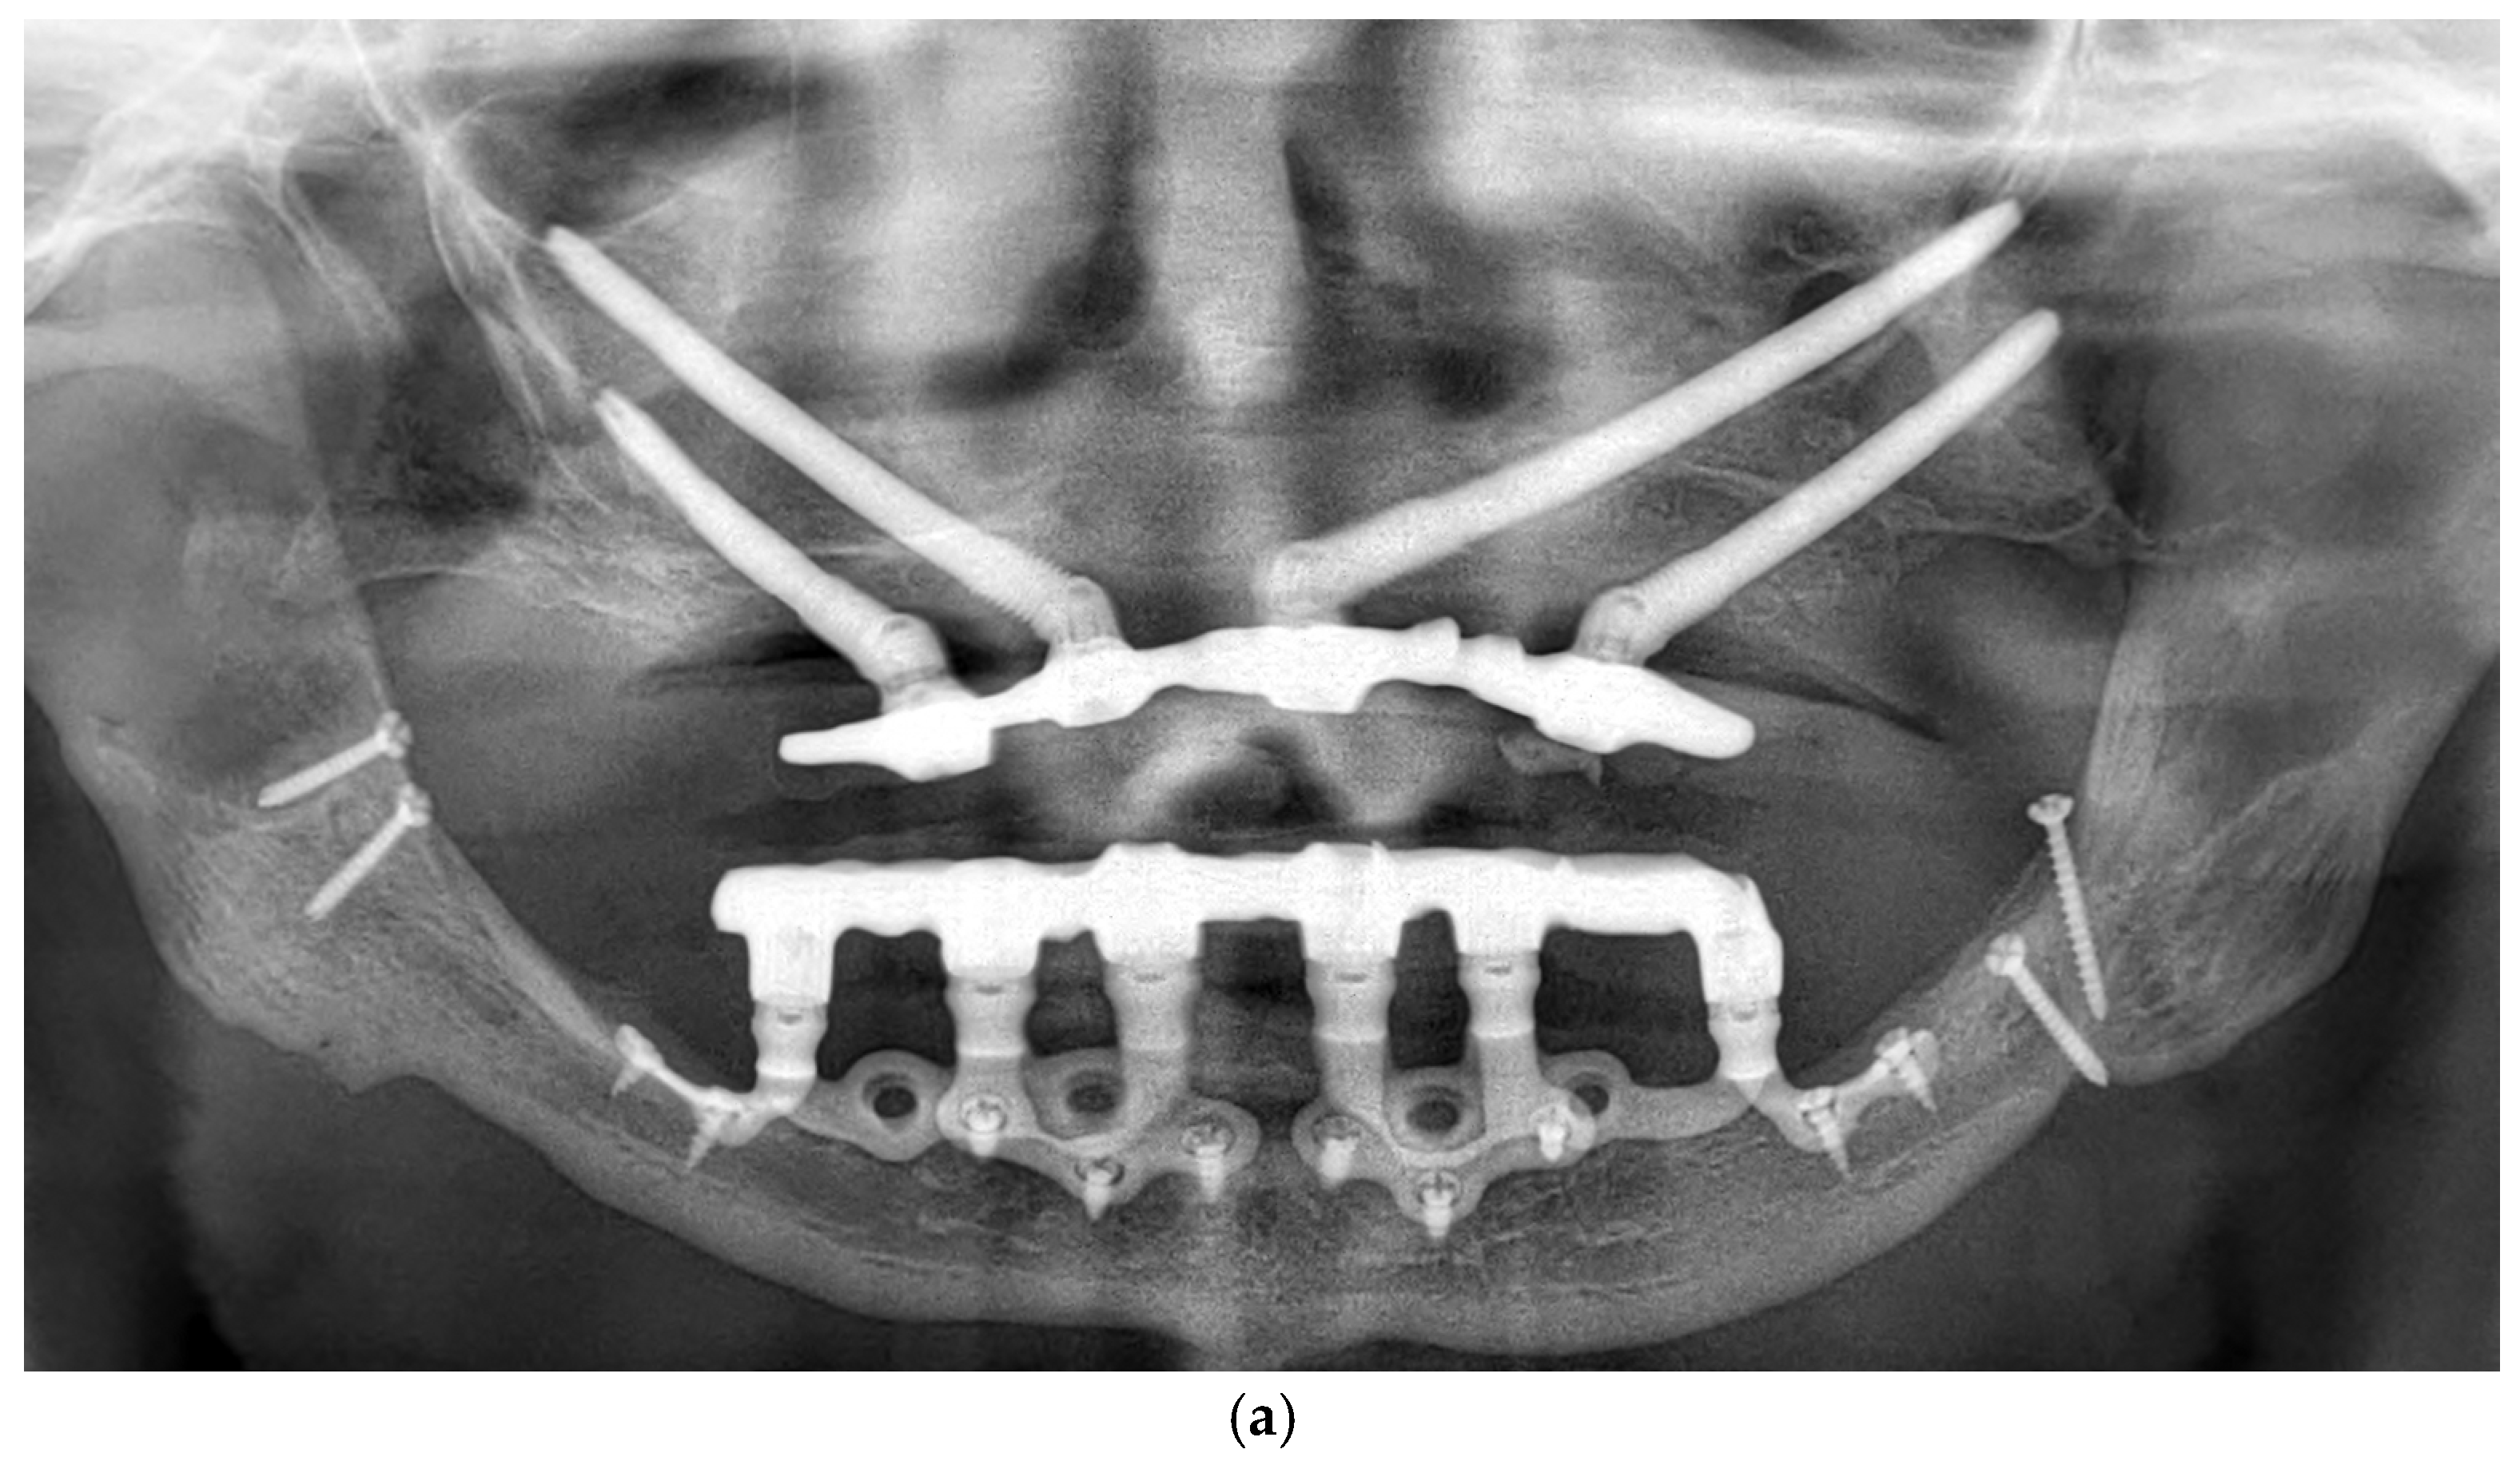

Patients were followed up at 3 and 6 months postoperatively, and then annually. Follow-up assessments included clinical evaluation and panoramic imaging; CBCT scans were obtained when necessary to monitor implant fit, peri-implant tissue response, and bone contour stability. All implants remained functionally stable throughout the observation period. The follow-up period ranged from 12 to 60 months, with a mean duration of 36.2 months (Figure 6a,b). Each patient underwent routine hygiene sessions every six months and an annual special session with prosthesis removal for thorough cleaning.

Figure 6.

(a) A panoramic radiograph of the patient at 5-year follow-up. (b) Intraoral clinical image of the patient at 5-year follow-up.